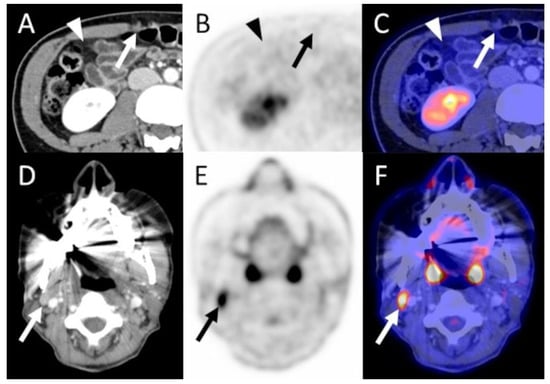

3.4.1. Primary Staging Patients (n = 15/52)

3.4.2. Restaging Patients (n = 17/52)

3.4.3. Recurrence Patients (n = 20/52)